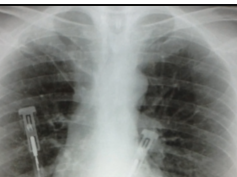

Clinical Case: Pulmonary Abscess